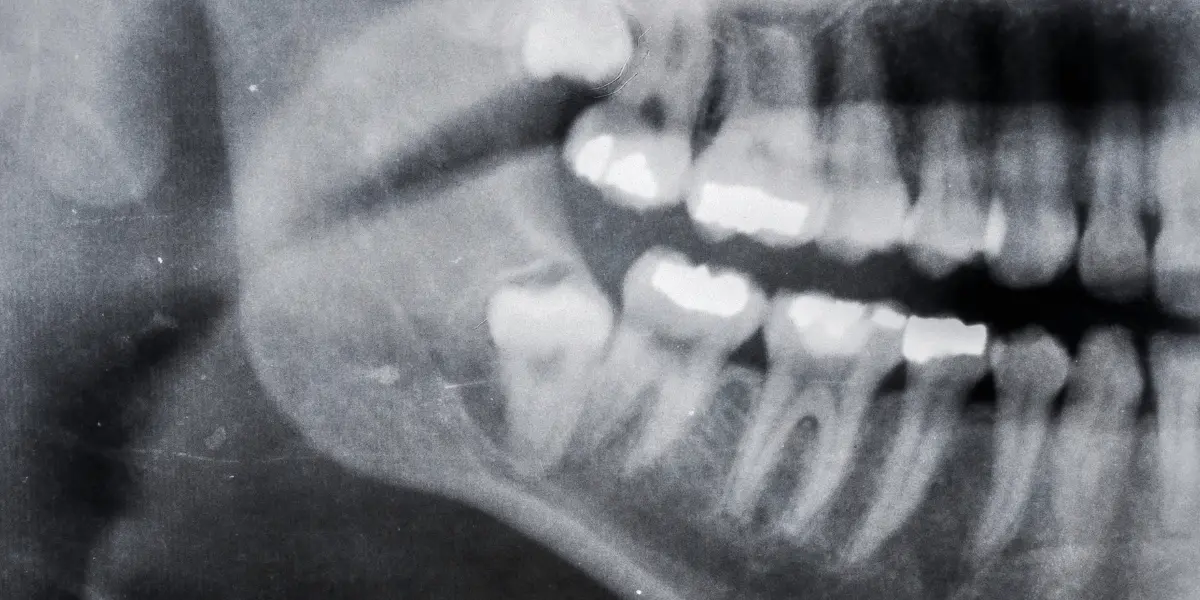

O diagnóstico é feito por um dentista, que pode fazer um exame clínico e radiográfico para determinar a posição do dente.

Para diagnosticar um dente abalado, o dentista irá realizar um exame clínico completo, avaliar os sintomas e pode solicitar exames de imagem, como radiografias ou tomografias, a fim de obter uma visão mais clara da posição do dente.

As radiografias podem mostrar a localização exata do dente afetado e se há algum dano aos dentes adjacentes.

Já as tomografias podem fornecer uma imagem 3D da área afetada, permitindo que o dentista visualize o dente em questão sob diferentes ângulos.

Durante o exame clínico, o dentista irá verificar se há algum dente que não tenha erupcionado ou que esteja parcialmente erupcionado.

O dentista também pode usar instrumentos especiais para verificar a posição do dente e determinar se é necessário realizar uma extração.